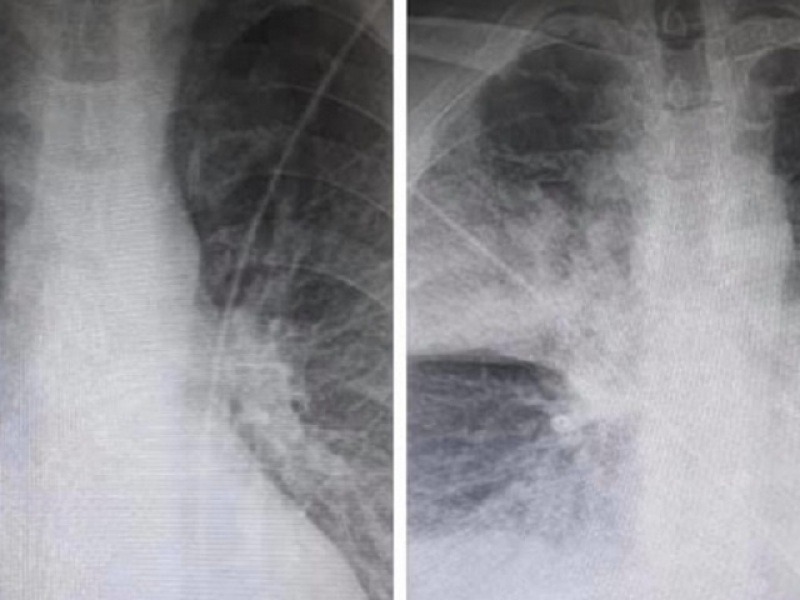

Σοκ προκαλούν οι δύο ακτινογραφίες που ανάρτησε στο Facebook ακτινολόγος από το ΚΑΤ, καθώς αποδεικνύουν την επίδραση που έχει ο κορωνοϊός στους πνεύμονες των ασθενών.

Όπως περιγράφει ο ακτινολόγος του ΚΑΤ Μάνος Καρράς οι δύο ακτινογραφίες ανήκουν σε έναν 38χρονο, ο οποίος είναι καπνιστής και διαβητικός. Σύμφωνα με τον ίδιο, οι ακτινογραφίες έχουν καταγραφεί με 7,5 ώρες διαφορά.

Η πρώτη είναι από την εισαγωγή στις 12 το μεσημέρι με 98% κορεσμό οξυγόνου και η δεύτερη, η επαναληπτική, πραγματοποιήθηκε στις 19:30 με τον ασθενή να είναι πλέον με μάσκα οξυγόνου.

Όπως εξηγεί σε σχόλιο στην ανάρτησή του ο κ. Καρράς, τα «σύννεφα» στη δεύτερη ακτινογραφία συνήθως σημαίνουν υγρό οίδημα φλεγμονή και «είναι κομμάτι του πνεύμονα που “δεν αναπνέει”».